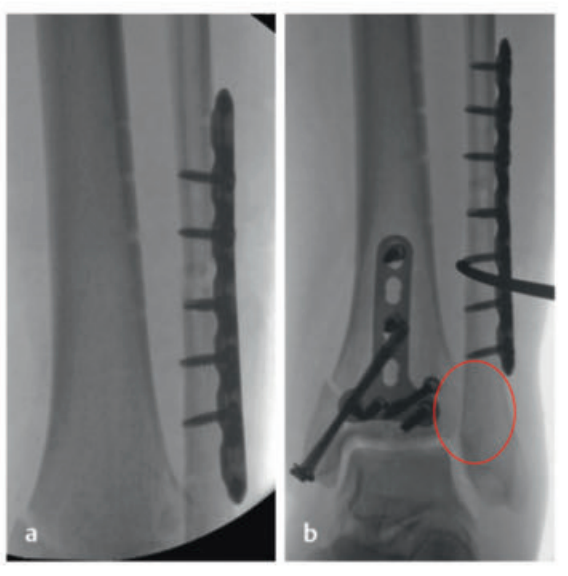

待软组织状况改善(出现 “皮肤皱纹征”)后,开始对患者进行手术治疗,首先处理腓骨(遵循 “先处理腓骨” 原则)。术中检查发现韧带联合存在不稳定情况。

术中三维CT 扫描确认骨折达到解剖复位,内植物位置良好。术后影像学检查证实骨折解剖复位,内植物位置正常。患者术后恢复过程顺利,关节功能恢复良好。